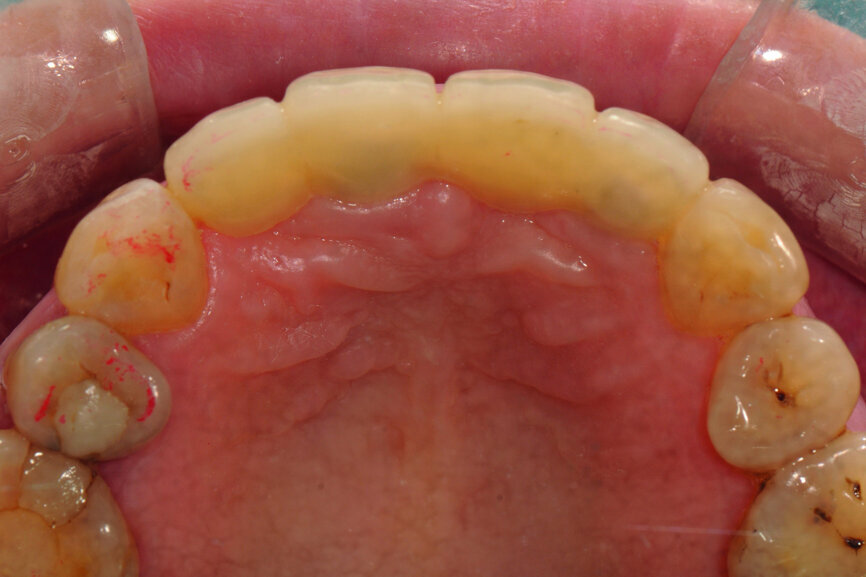

Fig. 15: Insertion of provisional abutments.

Fig. 16: Modification of the gingival contour under the pontic.

Fig. 17: Finishing of the reshaping of the gingiva.

Teeth #12, 21 and 22 were extracted. Tooth #11 underwent early implantation and tooth #22 immediate implantation with GBR (Figs. 5 & 6). After three months of healing, osseointegration had taken place. An implant level impression was taken for fabricating a provisional bridge supported by temporary abutments for teeth #12–22. The technician modified the shape of the artificial gingiva on the model in order to form the proper gingival curve and emergence profile, then finished the provisional bridge, while the dentist modified the gingival shape using an olive-shaped bur intraorally (Figs. 7–18).

In this case, we followed the second option. After using an olive-shaped bur to adjust the form of the gingiva under the pontic, making it match the provisional restoration, which had already been well designed and manufactured, a perfect soft-tissue outcome was achieved.